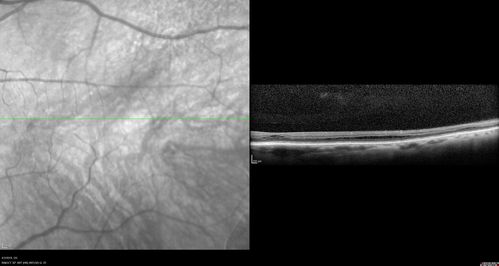

Stellate Non-heredtiary Idiopathic Foveomacular Retinoschisis (SNIFR)

77 year old man who is healthy and 6'6" tall with 20/40 vision and no complaints. OCT shows diffuse retinoschisis.